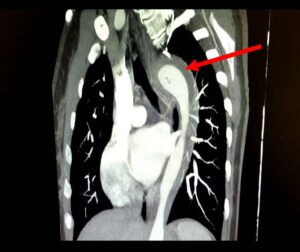

Uma mulher de 45 anos rompeu a aorta enquanto tinha relações sexuais com seu marido. O caso foi relatado da revista científica...